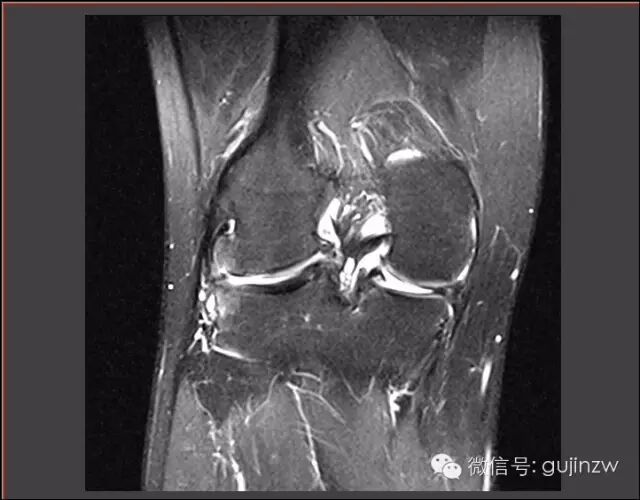

MRI

关节镜

病例1

• 男,23岁。

• 主诉:扭伤致右膝关节疼痛、活动受限2周

• 症状:右膝关节疼痛、活动受限,无弹响、交锁。

• 体征:活动屈曲轻度受限,浮髌试验阳性,外出关节间隙压痛。

• 被动挤压:麦氏征(+),Apley征(-)。

• 主动挤压:Ege‘s征(+),Thessaly 20°征(+)。